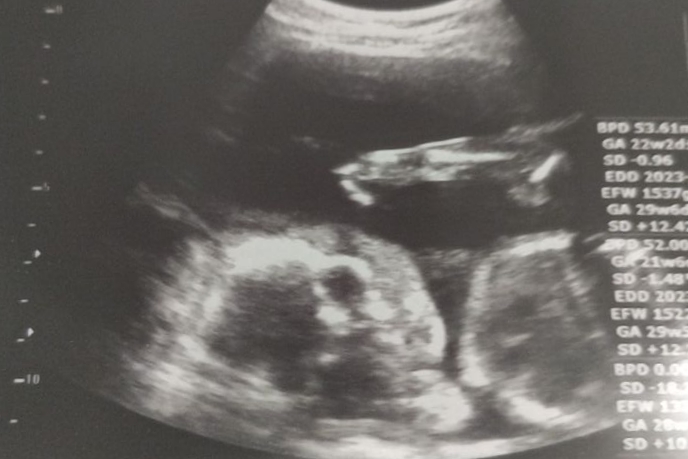

今回の検診で一応女の子っぽいと言われたみたいです👧 まあこればかりは絶対とは言えないところもあるみたいなのでお…

いやはやここまで順調になんとかきました~✨ いまいちはっきりとは性別わからず、今のところ女の子…かな~👧? ら…